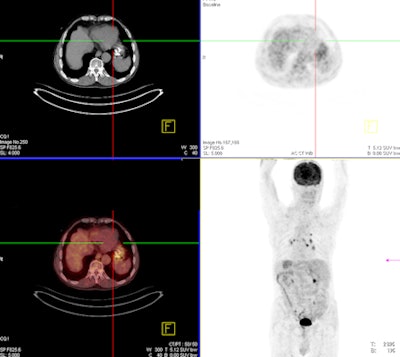

Specifically, Kantarci and colleagues examined the correlation between CT perfusion parameters and glucose metabolism as assessed by whole-body PET/CT and maximum standardized uptake values (SUVmax).

The study included 31 patients (19 men, 12 women; mean age, 59) who underwent FDG-PET/CT for esophageal cancer staging and also had CT perfusion and thoracoabdominal CT with contrast for esophageal masses. Eight of the patients had adenocarcinoma and 23 had squamous cell carcinoma. The study was conducted between May 2012 and November 2013.

Based on the CT perfusion and PET/CT images, the authors divided the esophageal tumors into three groups depending on tumor diameter: 5-15 mm (48%), 15-25 mm (32%), and 25-35 mm (19%).

CT perfusion parameters of blood volume, blood flow, and permeability surface were compared with SUVmax generated from PET, and tumor diagnosis was confirmed histopathologically in all patients. Correlations between tumor grade, pathological cell types, and SUVmax and CT perfusion parameters were assessed.

- For stage I disease, there was no measurable FDG uptake in four patients with tumors 6- to 12-mm in diameter. However, CT perfusion values were measured in all cases.

"The small tumors not detectable on PET/CT may be visible on CT perfusion," Kantarci concluded. "If there are presences of clinical suspicion and PET/CT findings are normal, CT perfusion imaging can be added to routine imaging examinations."